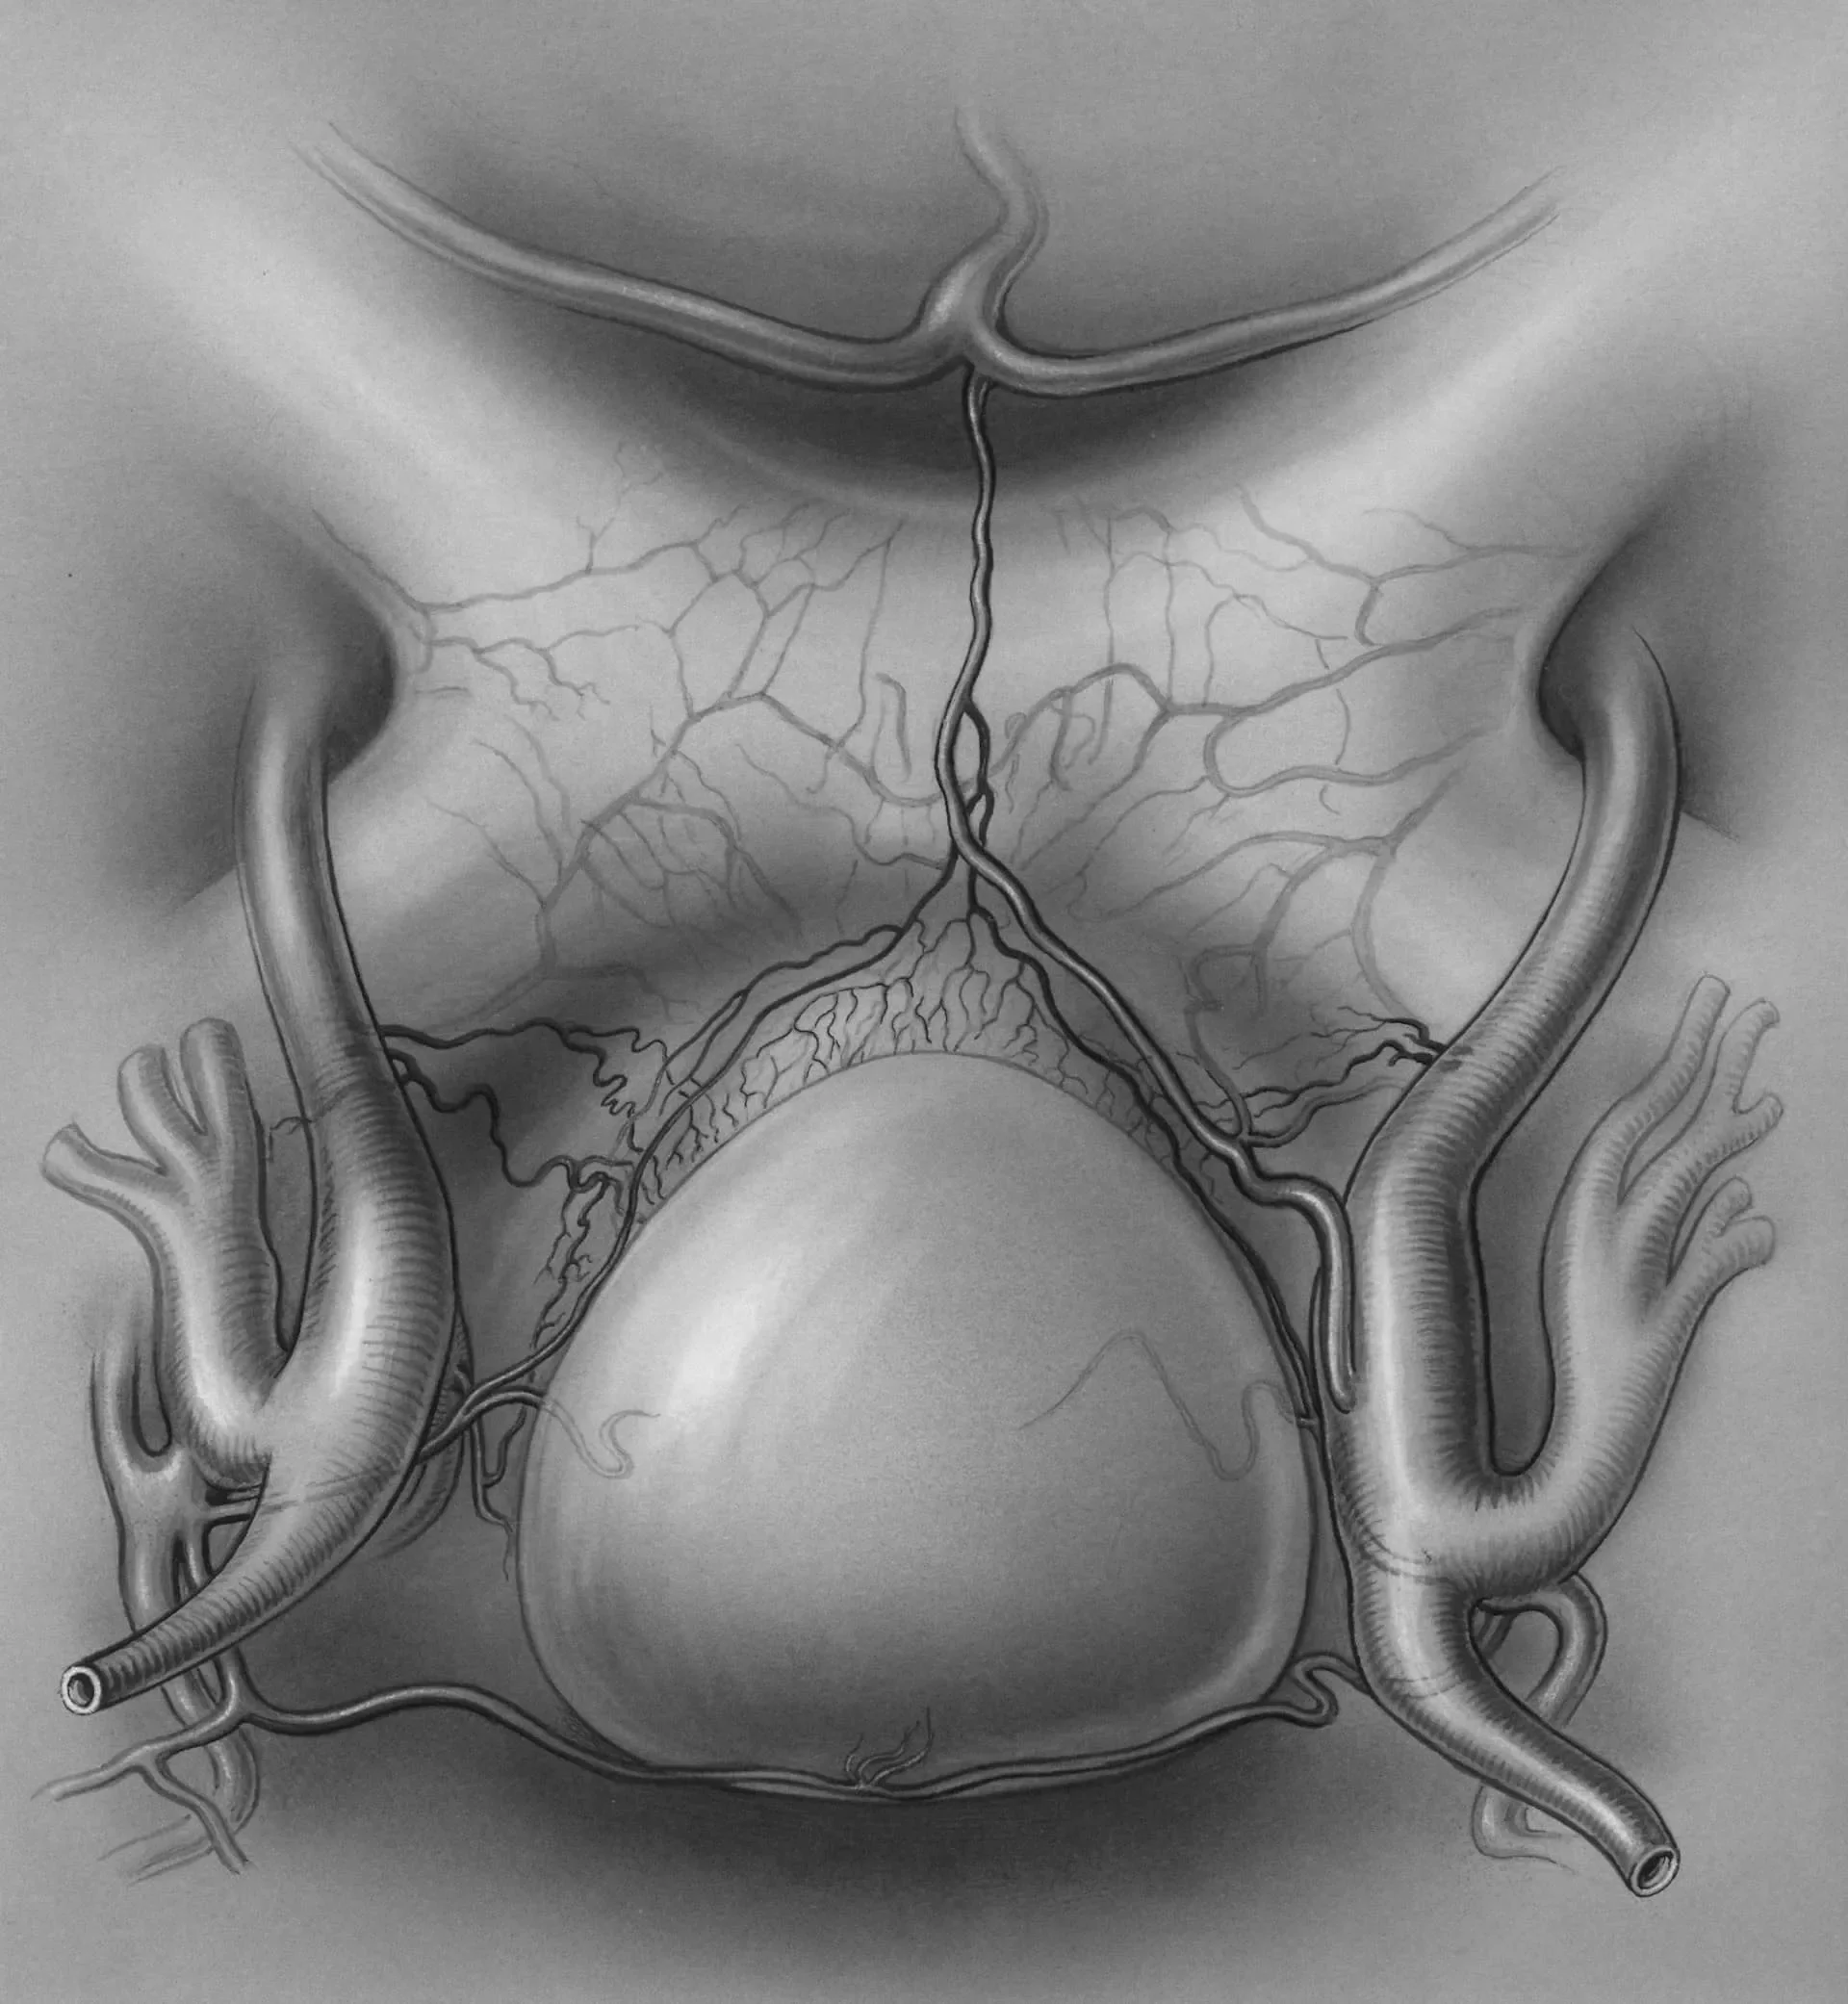

Medical illustration of the throat and esophagus used to explain the swallowing mechanism and dysphagia.

Instrumental Swallow Studies: When Imaging Is Needed

In some cases, a clinical swallow evaluation alone cannot fully visualize what's happening during the swallow. Nina may recommend an instrumental swallow study to obtain objective, detailed information about swallowing physiology.

Modified Barium Swallow Study (MBS/MBSS)

Also called a videofluoroscopic swallow study (VFSS), this is the gold standard for dysphagia assessment. During the study:

• You swallow foods and liquids mixed with barium (a safe contrast agent)

• Real-time X-ray imaging captures the entire swallow process

• Nina and a radiologist observe timing, coordination, and aspiration

• Therapeutic strategies are tested during the study to determine what works best

The MBS is performed at an outpatient radiology center. Nina coordinates scheduling and often attends the study to ensure continuity of care.